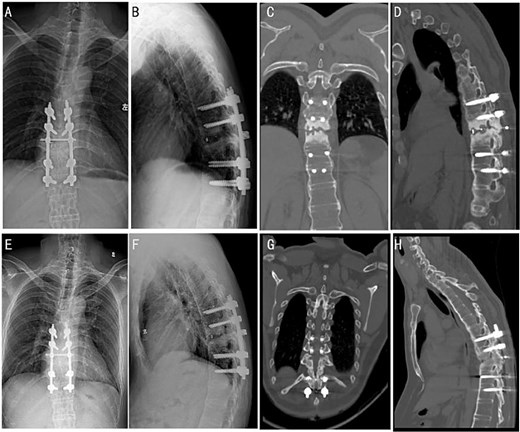

A 35-year-old male manual laborer presented to the spinal surgery department with a 5-year history of persistent chest pain and a 1-year history of progressive weakness and sensory disturbance in bilateral lower limbs. The patient denied any history of fever and trauma. Physical examination revealed marked kyphosis deformity of the thoracic spine and restricted spinal mobility. A neurological evaluation demonstrated reduced muscle strength in the left lower extremity (Grade II), bilateral positive “4” tests, and positive Babinski signs in both lower limbs. Laboratory investigation revealed HLA-B27 positivity. Inflammatory markers were elevated, with a sedimentation rate of 30 mm/h and a C-reactive protein level of 17 mg/l. Plain radiographs and computed tomography (CT) scans demonstrated the characteristic appearance of a “bamboo spine” that is consistent with advanced AS. A narrowed intervertebral space at T9-T10 vertebrae and prominent ossification of the paravertebral ligaments were observed (Fig. 1A–H). Magnetic resonance imaging (MRI) demonstrated the destruction of the T9-T10 vertebral bodies (Fig. 1I–N).

Preoperative imaging studies. (A and B) Full-length orthopantomogram of the spine. (C and D) Anteroposterior and lateral X-ray of the thoracic spine. (E and F) Sagittal and 3D reconstruction CT images (G and H) of the thoracic spine. Whole-spine MRI images of T1-weighted (I and J), T2-weighted (K and L), and short tau inversion recovery sequences (M and N), respectively.